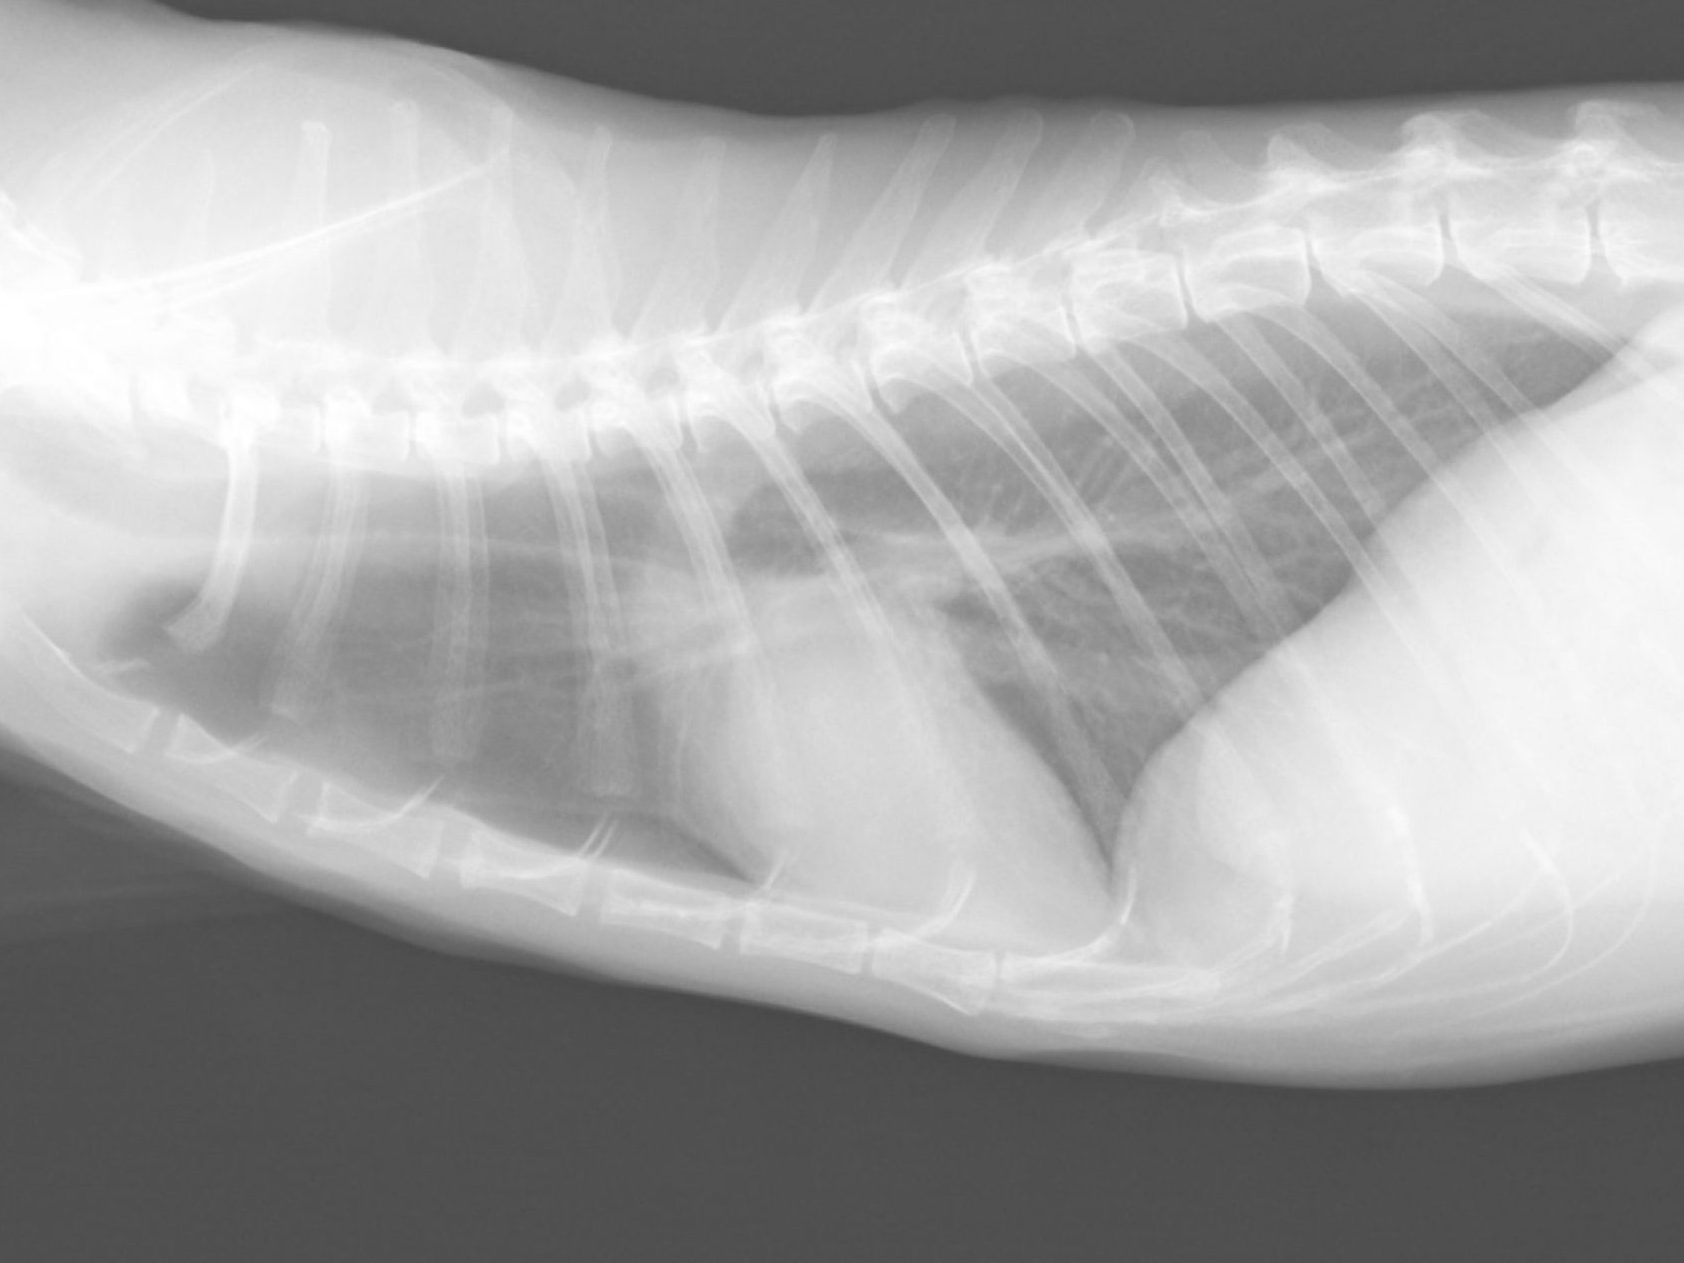

実際に胸水が溜まってしまった心筋症の子の胸部X線写真です。

呼吸が苦しそうで食事をとらないと来院され皮膚の外から針を指して胸水を抜くという緊急治療をしました。この時は300ml近く胸水がありました。